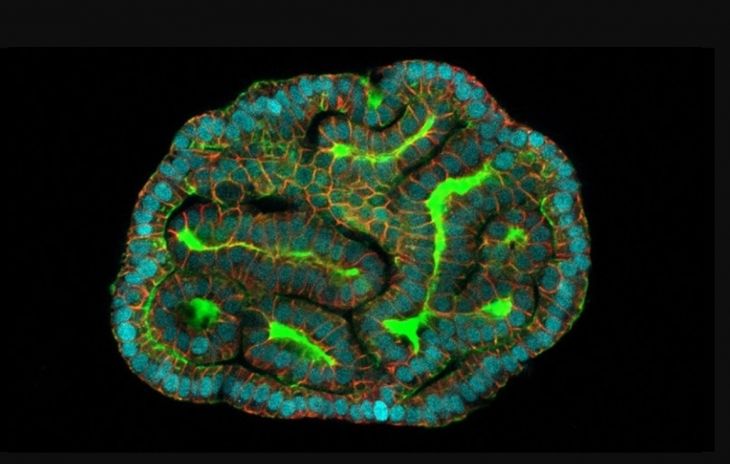

Científicos crearon miniórganos a partir de células que flotan en el líquido que rodea al feto en el útero, avance que consideran que podría abrir nuevas áreas de la medicina prenatal.

Los miniórganos u “organoides” son pequeñas estructuras simplificadas que pueden usarse para probar nuevos tratamientos médicos o estudiar cómo funcionan los órganos reales que imitan, ya sean sanos o enfermos.

Investigadores del Colegio Universitario de Londres y del Hospital de la Calle Great Ormond, también de Reino Unido, recolectaron células de muestras de líquido amniótico tomadas en 12 embarazos como parte de pruebas prenatales de rutina. Luego, por primera vez, desarrollaron miniórganos a partir de células extraídas durante gestaciones activas. Imaginan que su enfoque podría eventualmente ayudar a los médicos a vigilar y tratar condiciones congénitas antes del nacimiento y desarrollar terapias personalizadas para un bebé en el útero.

Las células madres específicas de tejido que Gerli y sus colegas recolectaron fueron eliminadas por el feto, como ocurre durante el embarazo. Los científicos identificaron de qué tejidos procedían y encontraron células de los pulmones, los riñones y los intestinos.

Los investigadores cultivaron organoides pulmonares a partir de células de fetos con la afección antes y después del tratamiento y los compararon con organoides de fetos sanos.